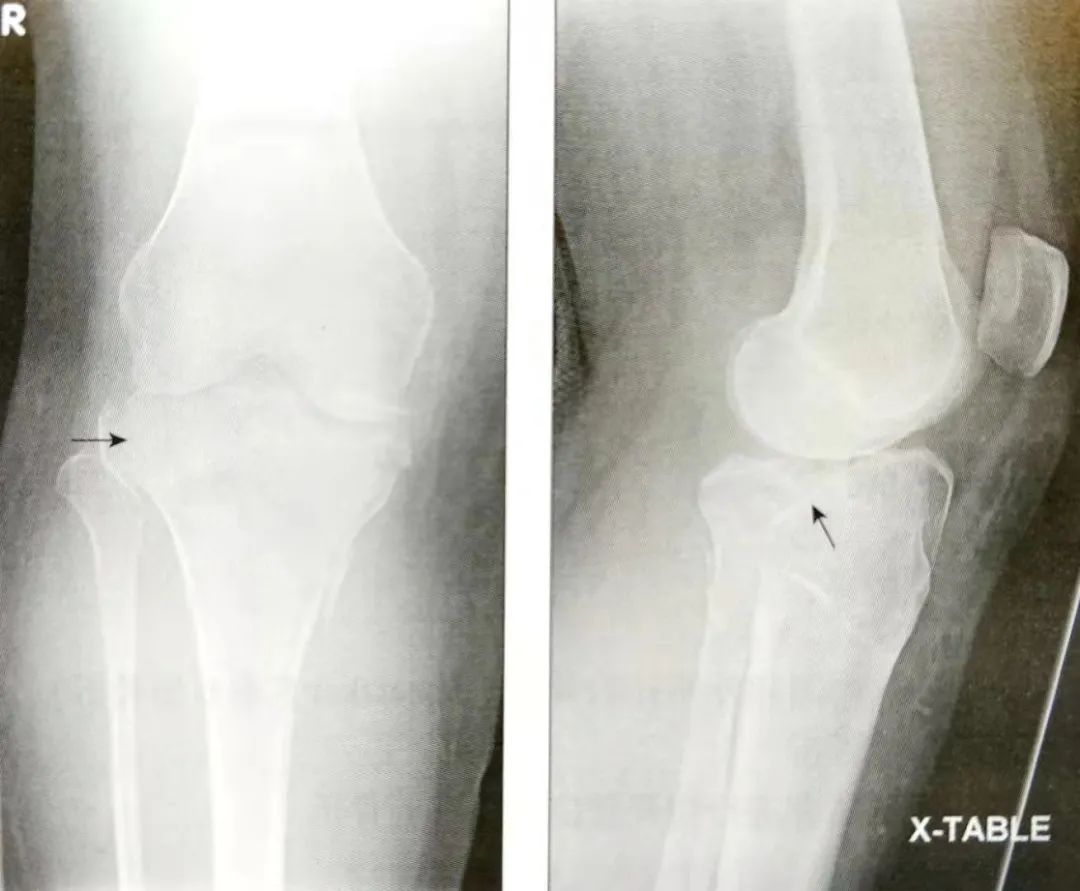

拍摄胫腓骨Ⅹ线平片;

评估膝关节半脱位的程度。

评估胫骨髁间嵴骨折,它在侧位片上显示最清楚;

观察胫骨平台的塌陷,正位片和侧位片。

A:正位片;B:侧位片